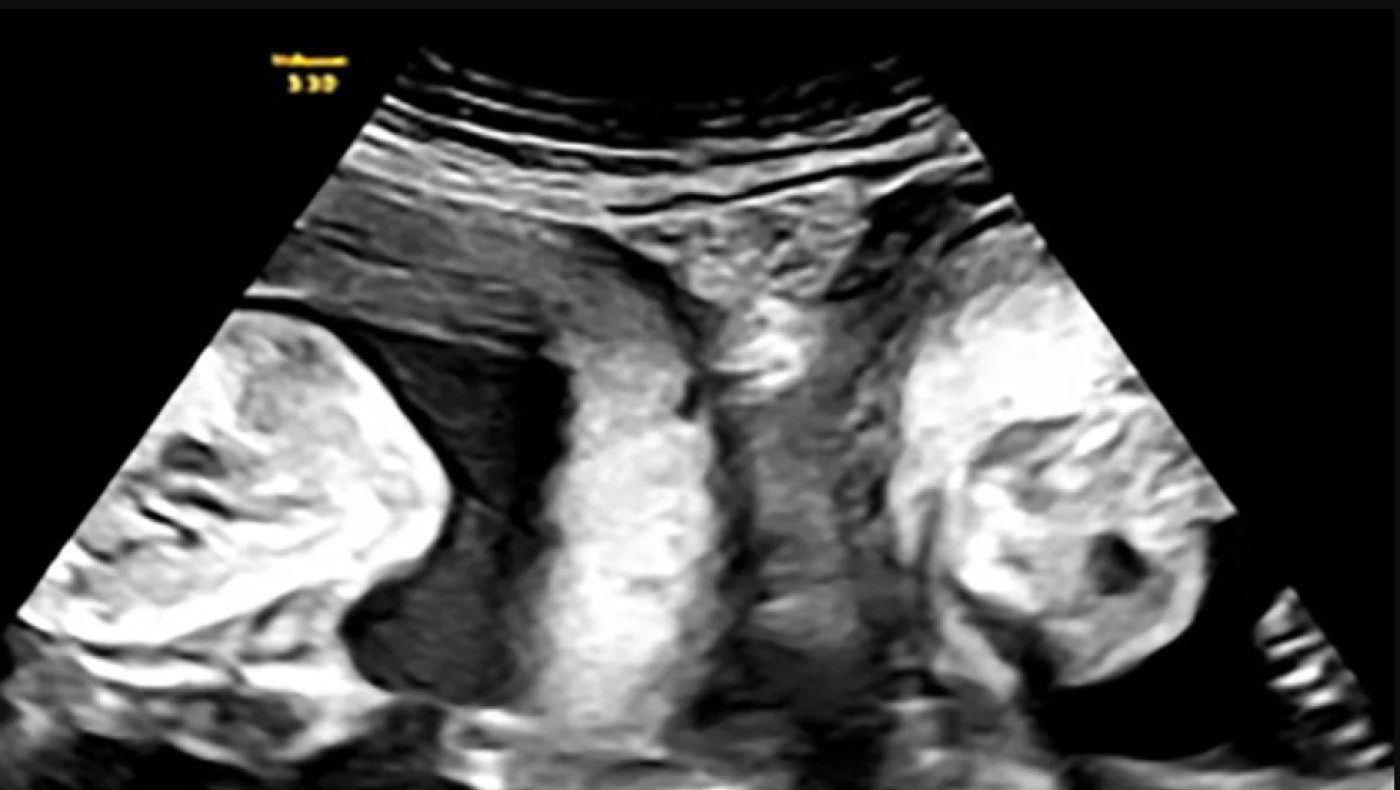

Σύμφωνα με το νοσοκομείο, η νέα μητέρα γεννήθηκε με δύο τραχήλους και δύο μήτρες, μια κατάσταση που ονομάζεται δίδελφυς μήτρα και συναντάται σε περίπου 1 στις 2.000 γυναίκες.

Τον Ιανουάριο, όμως, η Li έμεινε ξανά έγκυος και ανακάλυψε κατά τη διάρκεια ενός υπερηχογραφήματος ότι κυοφορούσε δίδυμα - ένα σε κάθε μήτρα και οι γιατροί του νοσοκομείου «έπεσαν» πάνω στο περιστατικό για να εξασφαλίσουν την επιτυχία της εγκυμοσύνης.